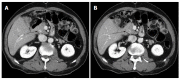

Extrahepatic bile duct (EHBD) cancer may occur metachronously, and these cancers are resectable with a favorable prognosis. We aimed to identify the pattern of metachronous EHBD cancer. We classified the cases of metachronous EHBD cancer reported in the literature thus far and investigated two new cases of metachronous EHBD cancer. A 70-year-old female underwent R0 bile duct resection for a type 1 Klatskin tumor (pT1N0M0). A 70-year-old male patient underwent R0 bile duct resection for a middle bile duct cancer (pT2N1M0). Imaging studies of both patients taken at 14 and 24 mo after first surgery respectively revealed a metachronous cholangiocarcinoma that required pancreaticoduodenectomy (PD). Histopathology of the both tumors after PD revealed cholangiocarcinoma invading the pancreas (pT3N0M0). Both patients have been free from recurrence for 6 years and 16 mo respectively after the second surgery. Through a review of the literature on these cases, we classified the pattern of metachronous EHBD cancer according to the site of de novo neoplasia. The proximal remnant bile duct was most commonly involved. Metachronous EHBD cancer should be distinguished from an unresectable recurrent tumor. Classifying metachronous EHBD cancer may be helpful in identifying rare metachronous tumors.